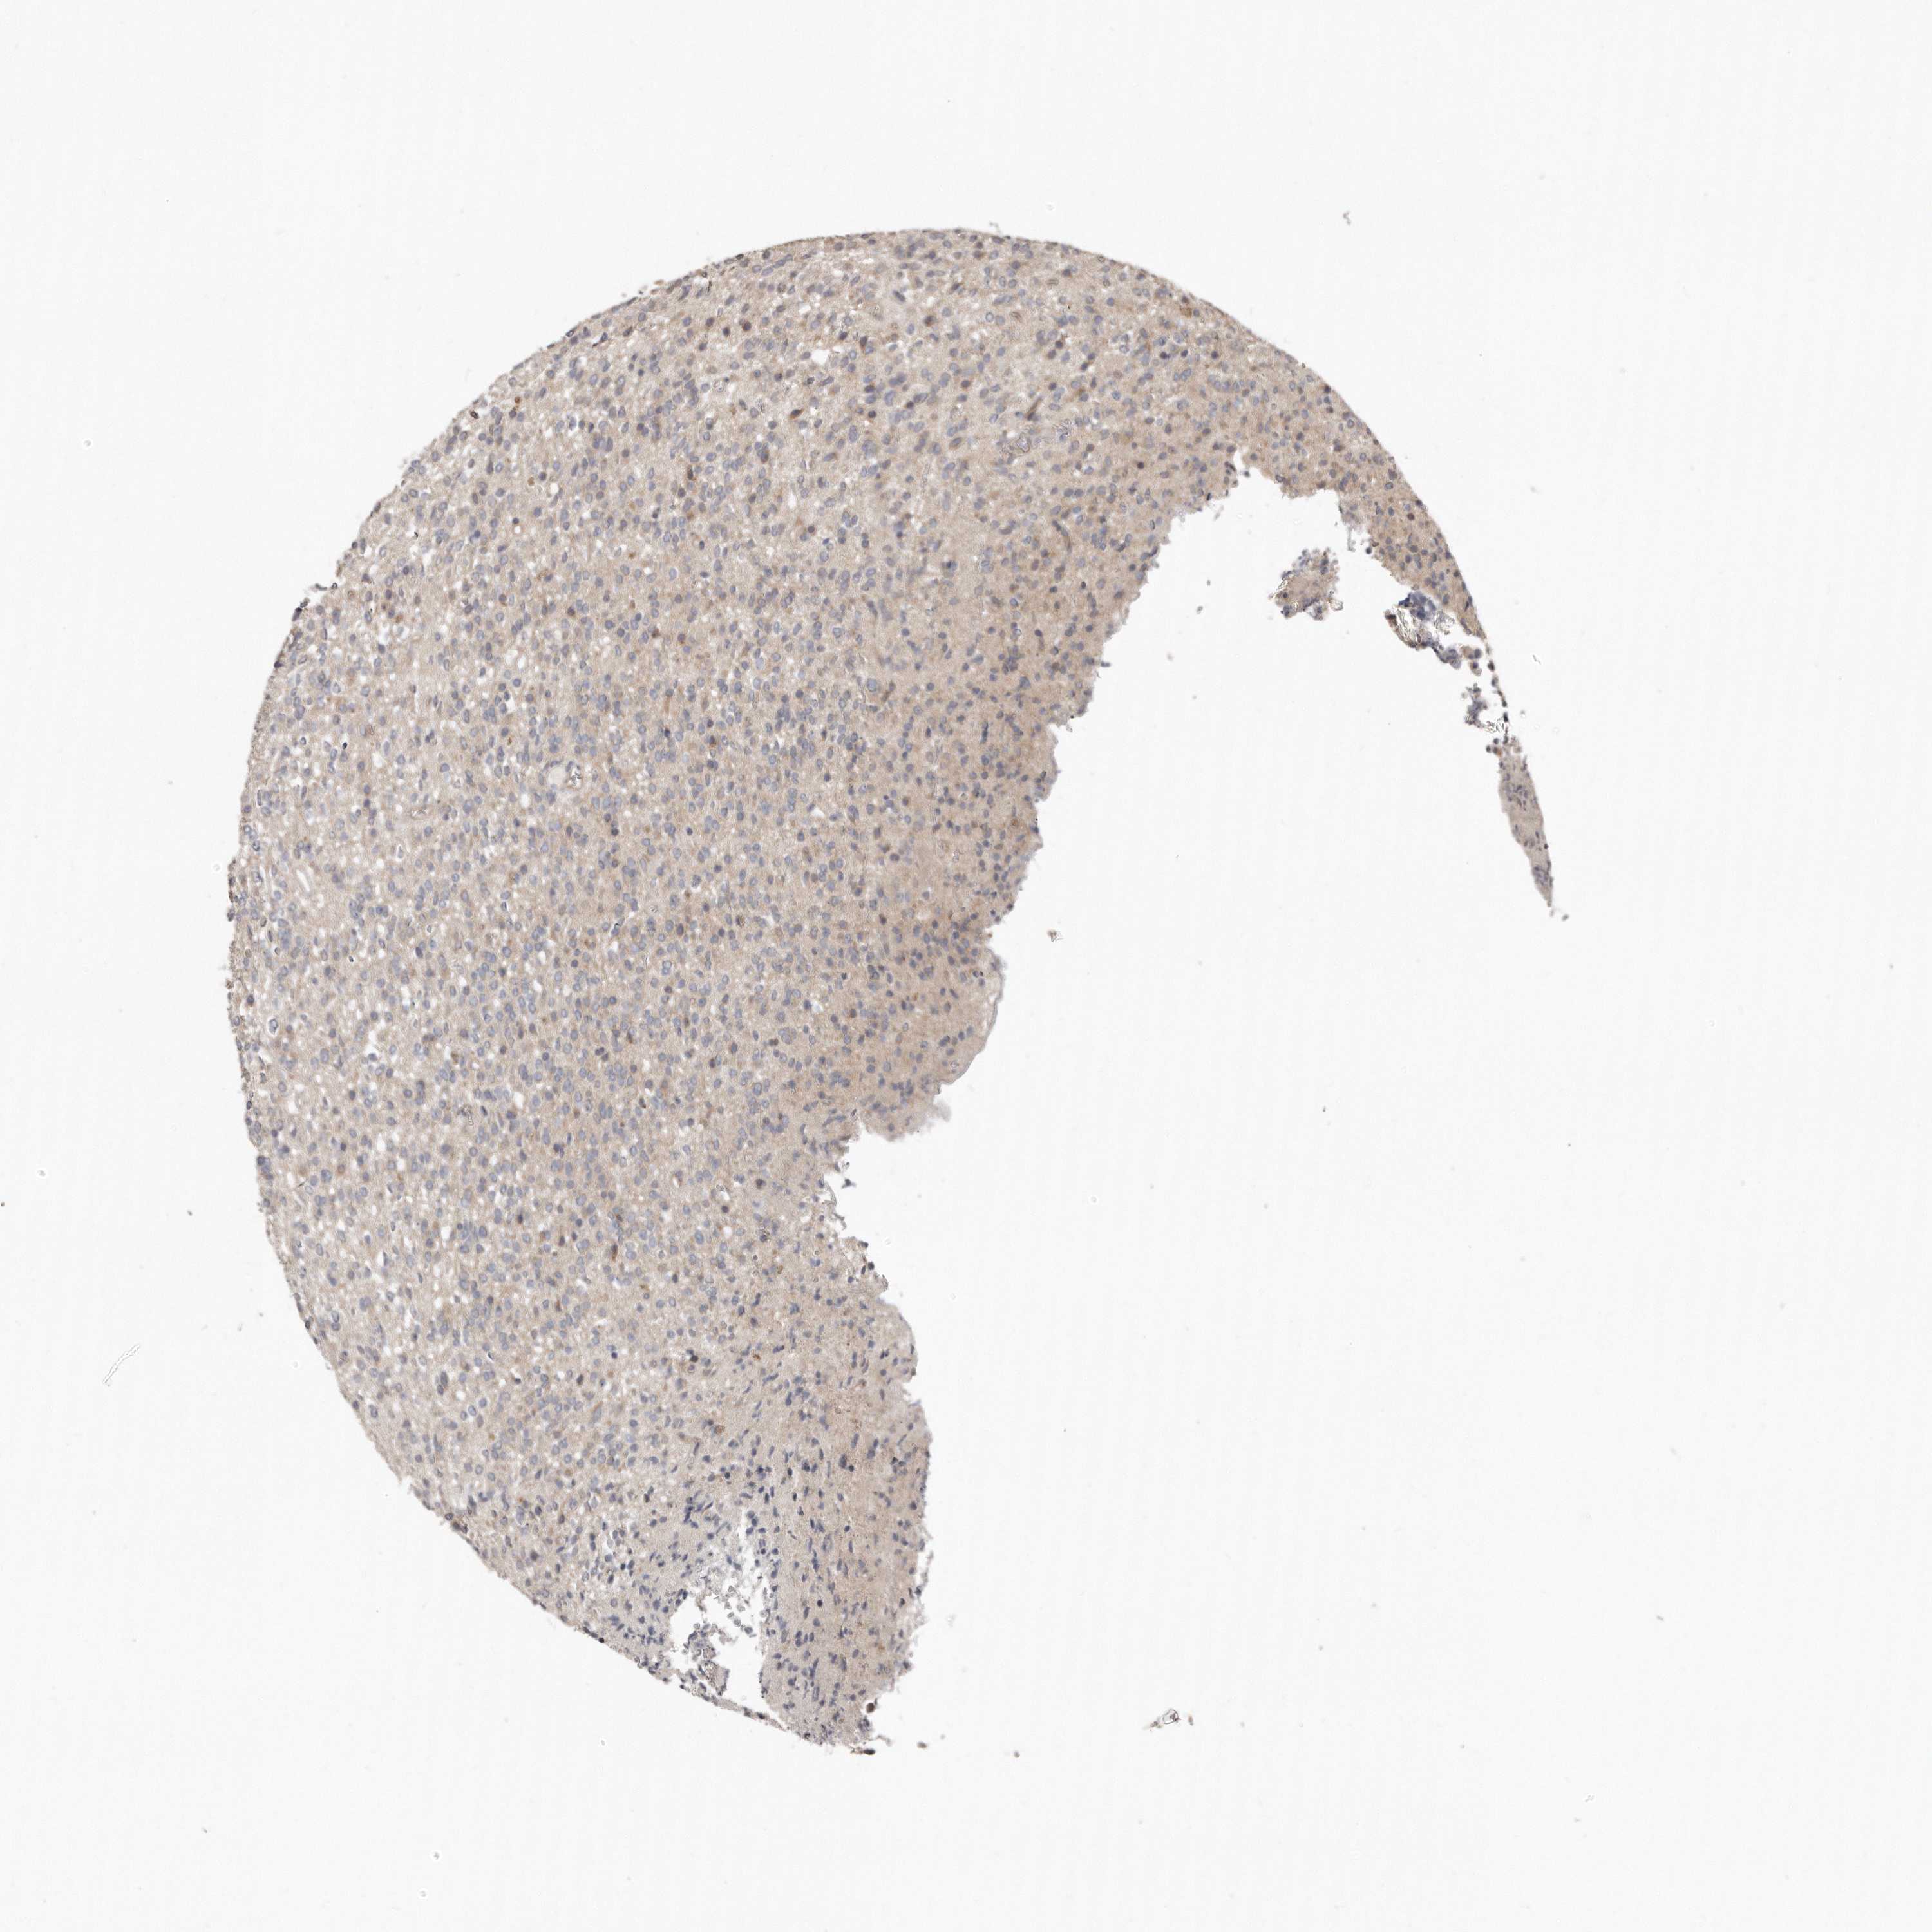

GLIOMA - Protein expressioni

A mouse-over function shows sample information and annotation data. Click on an image to view it in a full screen mode. Samples can be filtered based on level of antibody staining by selecting one or several of the following categories: high, medium, low and not detected. The assay and annotation is described here.

Note that samples used for immunohistochemistry by the Human Protein Atlas do not correspond to samples in the TCGA dataset.

Antibody stainingi

Antibody staining in the annotated cell types in the current human tissue is reported as not detected, low, medium, or high, based on conventional immunohistochemistry profiling in selected tissues. This score is based on the combination of the staining intensity and fraction of stained cells.

Each image is clickable and will lead to virtual microscopy that enables deeper exploration of all samples and also displays staining intensity scores, fraction scores and subcellular localization as well as patient and tissue information for each sample.

Antibody HPA030270

Antibody HPA030271

Antibody HPA030272

Staining

High

Medium

Low

Not detected

Intensity

Strong

Moderate

Weak

Negative

Quantity

>75%

75%-25%

<25%

None

Location

Nuclear

Cytoplasmic/membranous

Cytoplasmic/membranous,nuclear

Glioma, malignant, High grade

Glioma, malignant, Low grade

Glioblastoma, NOS